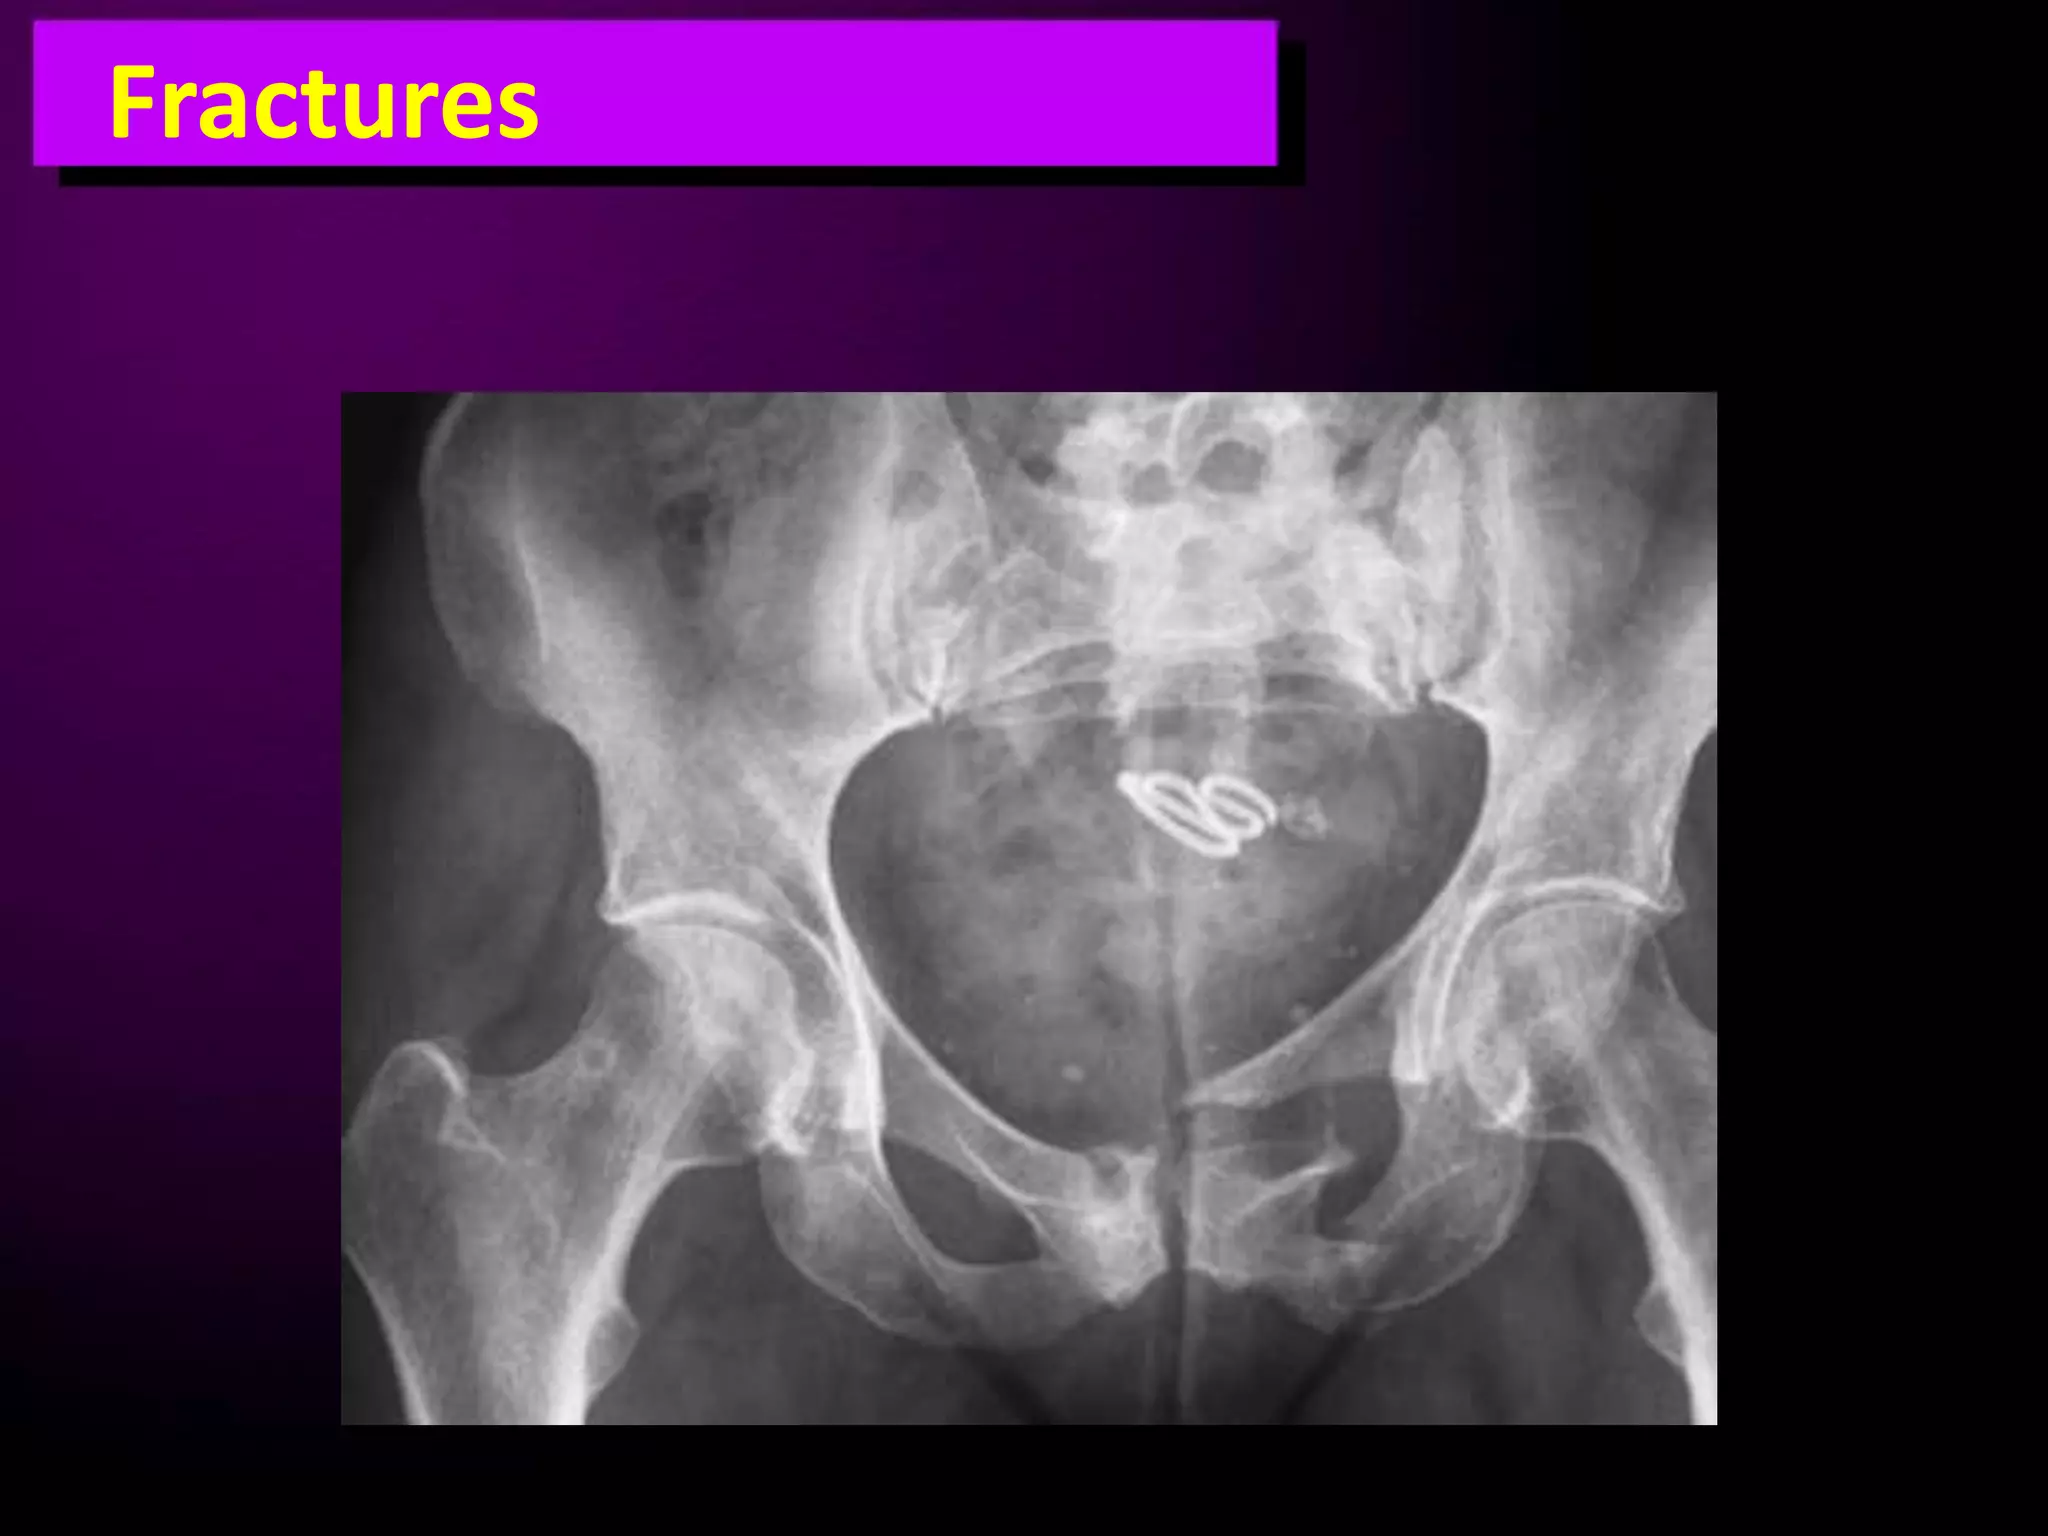

This document discusses trauma to the pelvis, hips, knees, ankles, and feet. It covers anatomy, imaging techniques, and types of fractures and dislocations that can occur in these areas. The types of fractures discussed include pelvic ring fractures, acetabular fractures, and fractures of the femur, tibia, fibula, and bones of the foot. Imaging views used include AP, inlet, and outlet views of the pelvis. Dislocations and fractures of the knee, ankle, and foot joints are also examined.